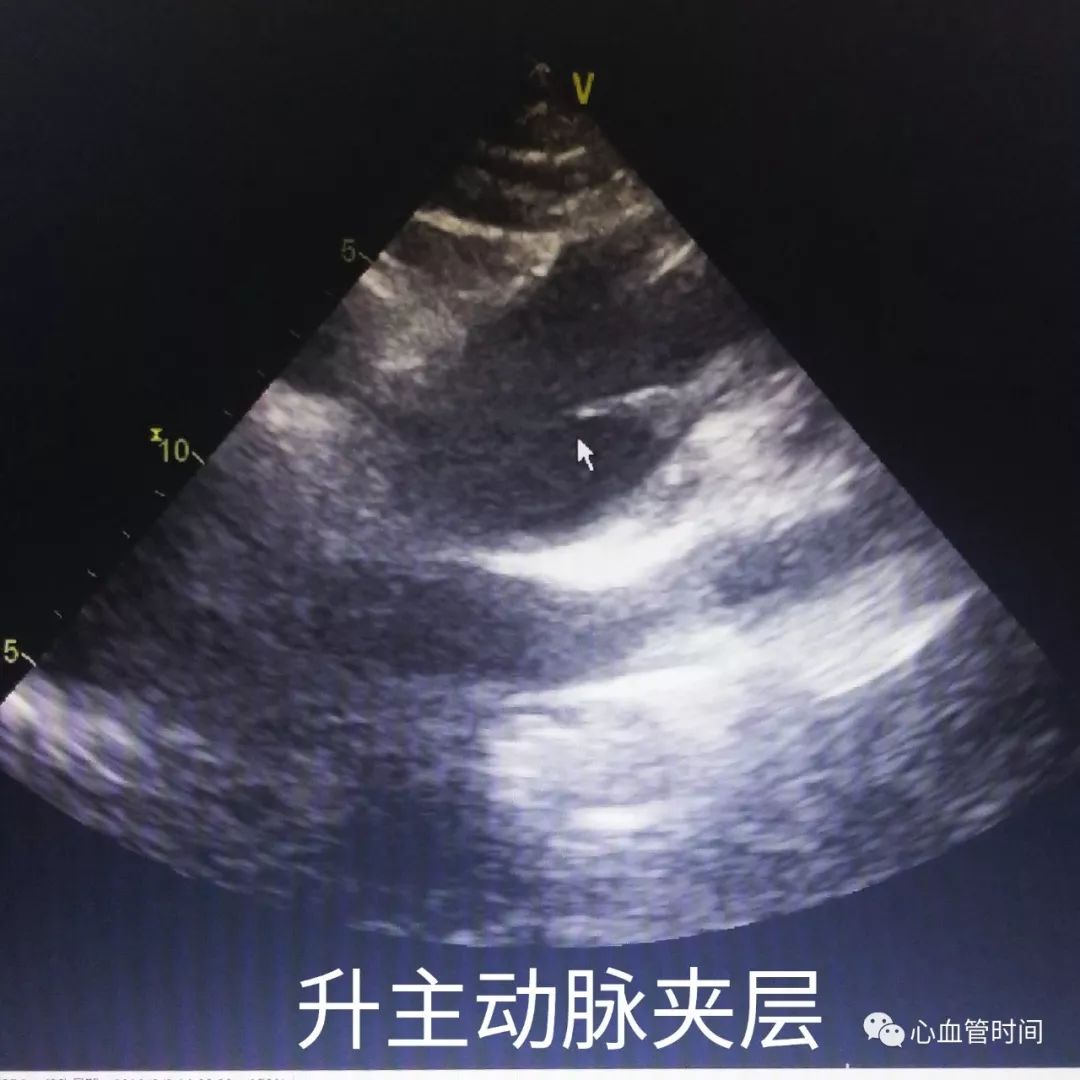

升主动脉升主动脉若明显增宽,且出现

片状回声时要考虑夹层可能,但需注意该切面往往出现

伪像较多,有个别患者超声可见明显飘动片状影,CTA 却未见异常。

升主动脉升主动脉若明显增宽,且出现

片状回声时要考虑夹层可能,但需注意该切面往往出现

伪像较多,有个别患者超声可见明显飘动片状影,CTA 却未见异常。